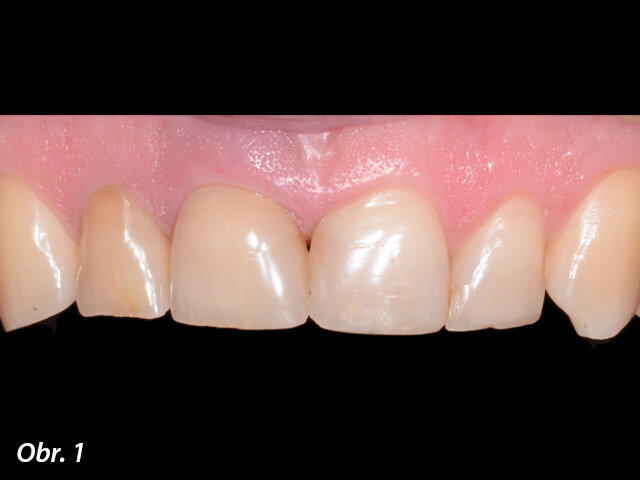

CBCT snímek, na kterém je vidět fraktura kořene zubu i vnější resorpce kořene z vestibulární strany.

47letý pacient byl odeslán na kliniku s prasklým kořenem zubu 11. Provedené CBCT vyšetření dále odhalilo zevní resorpci kořene. Léčebný plán se zakládal na provedení okamžité implantace s použitím estetické implantologicko-protetické rekonstrukce.